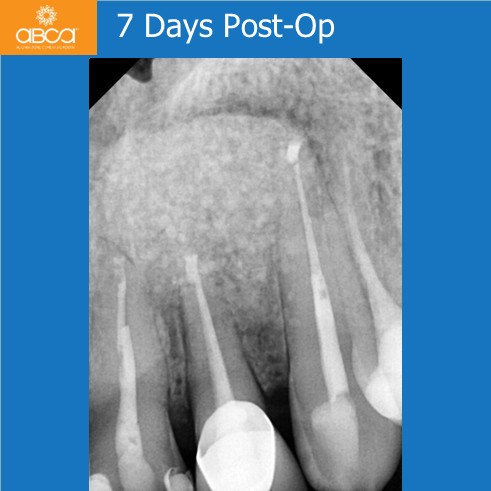

Radiographic examination revealed a large bone defect with damage to both cortical plates. We performed root resection of teeth #21 (9), #22 (10), and #23 (11), and backfilled the root canals with MTA. After cyst enucleation, the cyst is sent for histopathological examination, which confirmed a radicular cyst. Filling of the bone defect with 3 cc of Bond Apatite®.